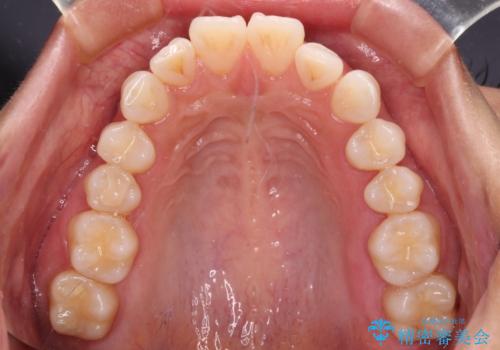

尖った前歯を引っ込めたい 目立たないワイヤー装置での抜歯矯正

- 飛び出した前歯を気にして来院された患者様です。

口元を引っ込めるために上下左右の第一小臼歯4本を抜歯することとしました。

途中妊娠と出産がありましたが、予定よりも早く治療を終えることができました。